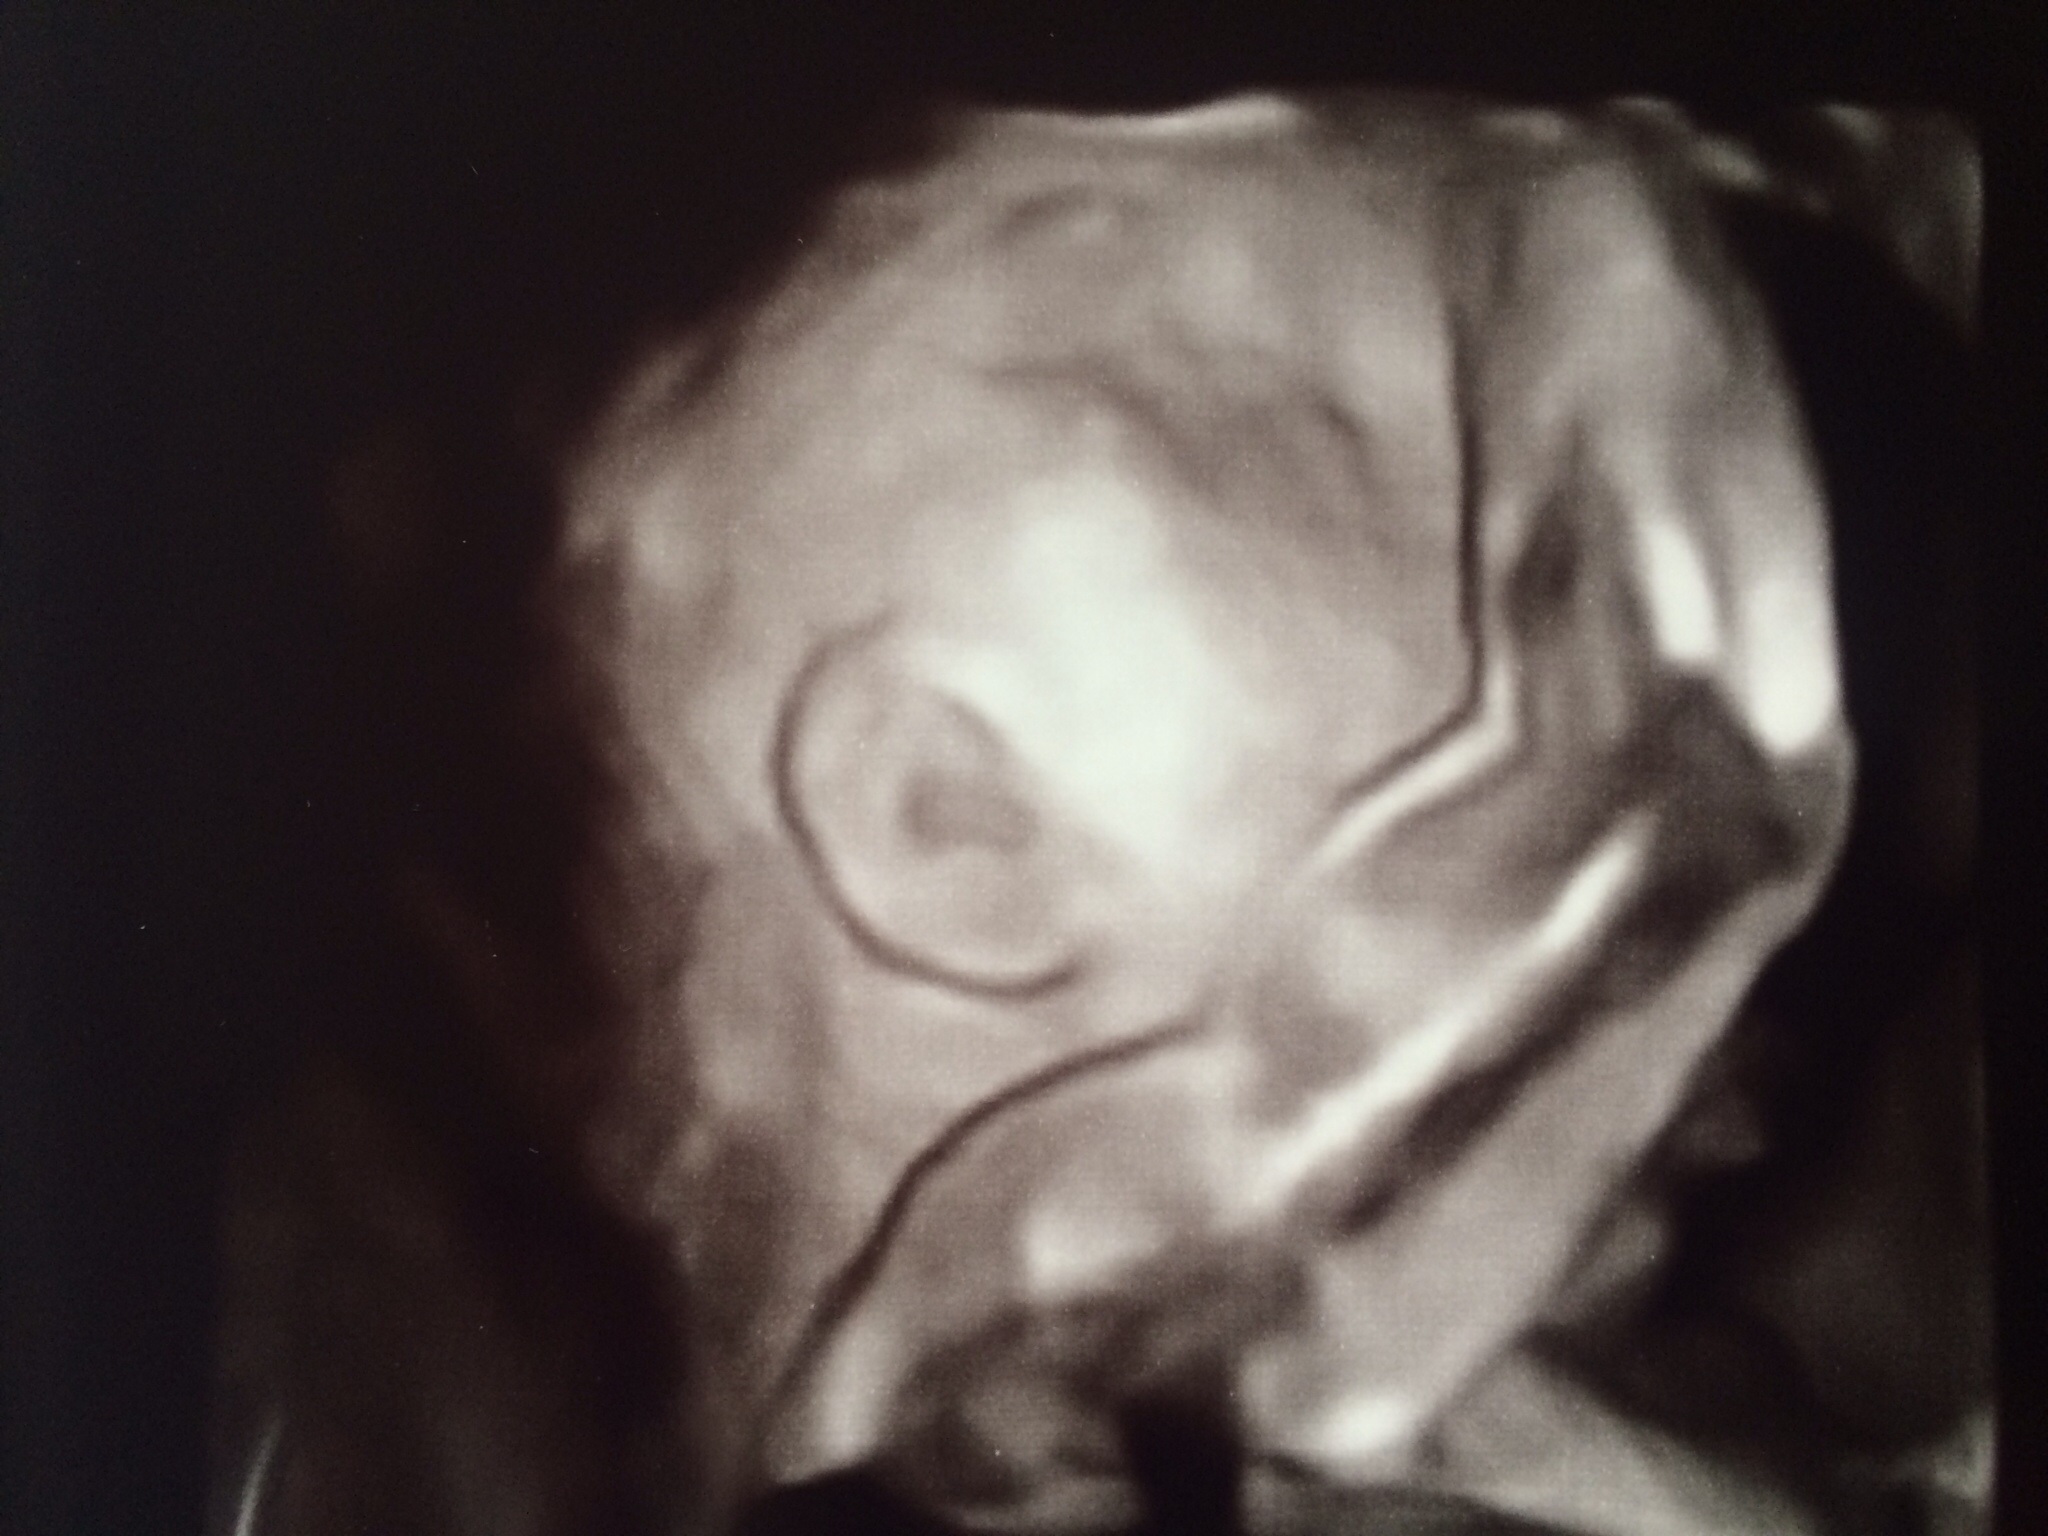

Mine also covered his face, with his hand, but we could see a little bit. Then after 2 weeks the regular ultrasound check, we saw his face and it was amazing.

OP, even though you can't see your baby boy's face, that's a really cute picture.